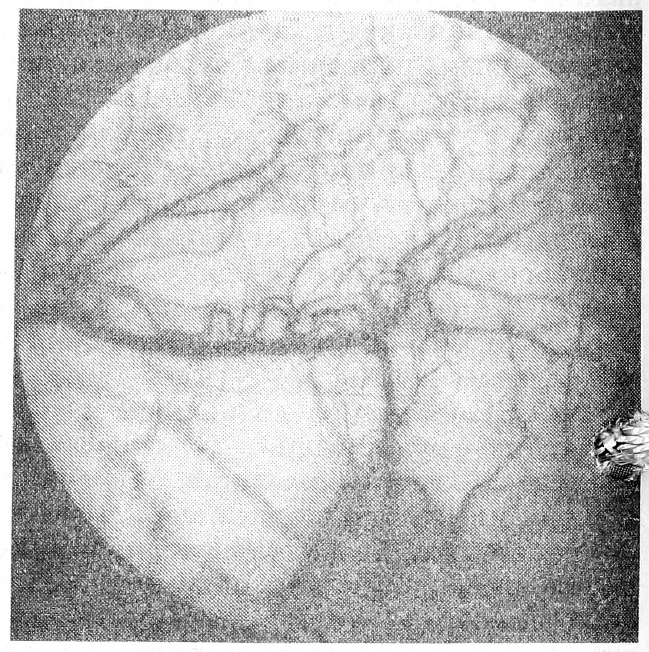

Гиперкоагуляционные сдвиги были обнаружены у 88% больных. Нарушения в системе микроциркуляции корригировали не только традиционными средствами лечения, но и антикоагулянтами, а также препаратами, восстанавливающими реологические свойства крови (гепарин, фибринолизин, курантил). В процессе терапии отмечалось улучшение в состоянии микроциркуляции. Так, феномен «сладжа» наблюдался лишь в мелких капиллярах и венулах (рис. 2), однако в большинстве случаев сохранялись периваскулярные и сосудистые изменения. У больных хроническим необструктивным бронхитом и острой пневмонией легкой и тяжелой степени определялась более положительная динамика, чем у больных хроническим обструктивным бронхитом и острой пневмонией средней тяжести, что требовало дальнейшего диспансерного наблюдения за последними и проведения им амбулаторного лечения для предупреждения хронизации воспалительного процесса.

Рис. 2. Микрофотография бульбарной конъюнктивы того же больного после лечения.